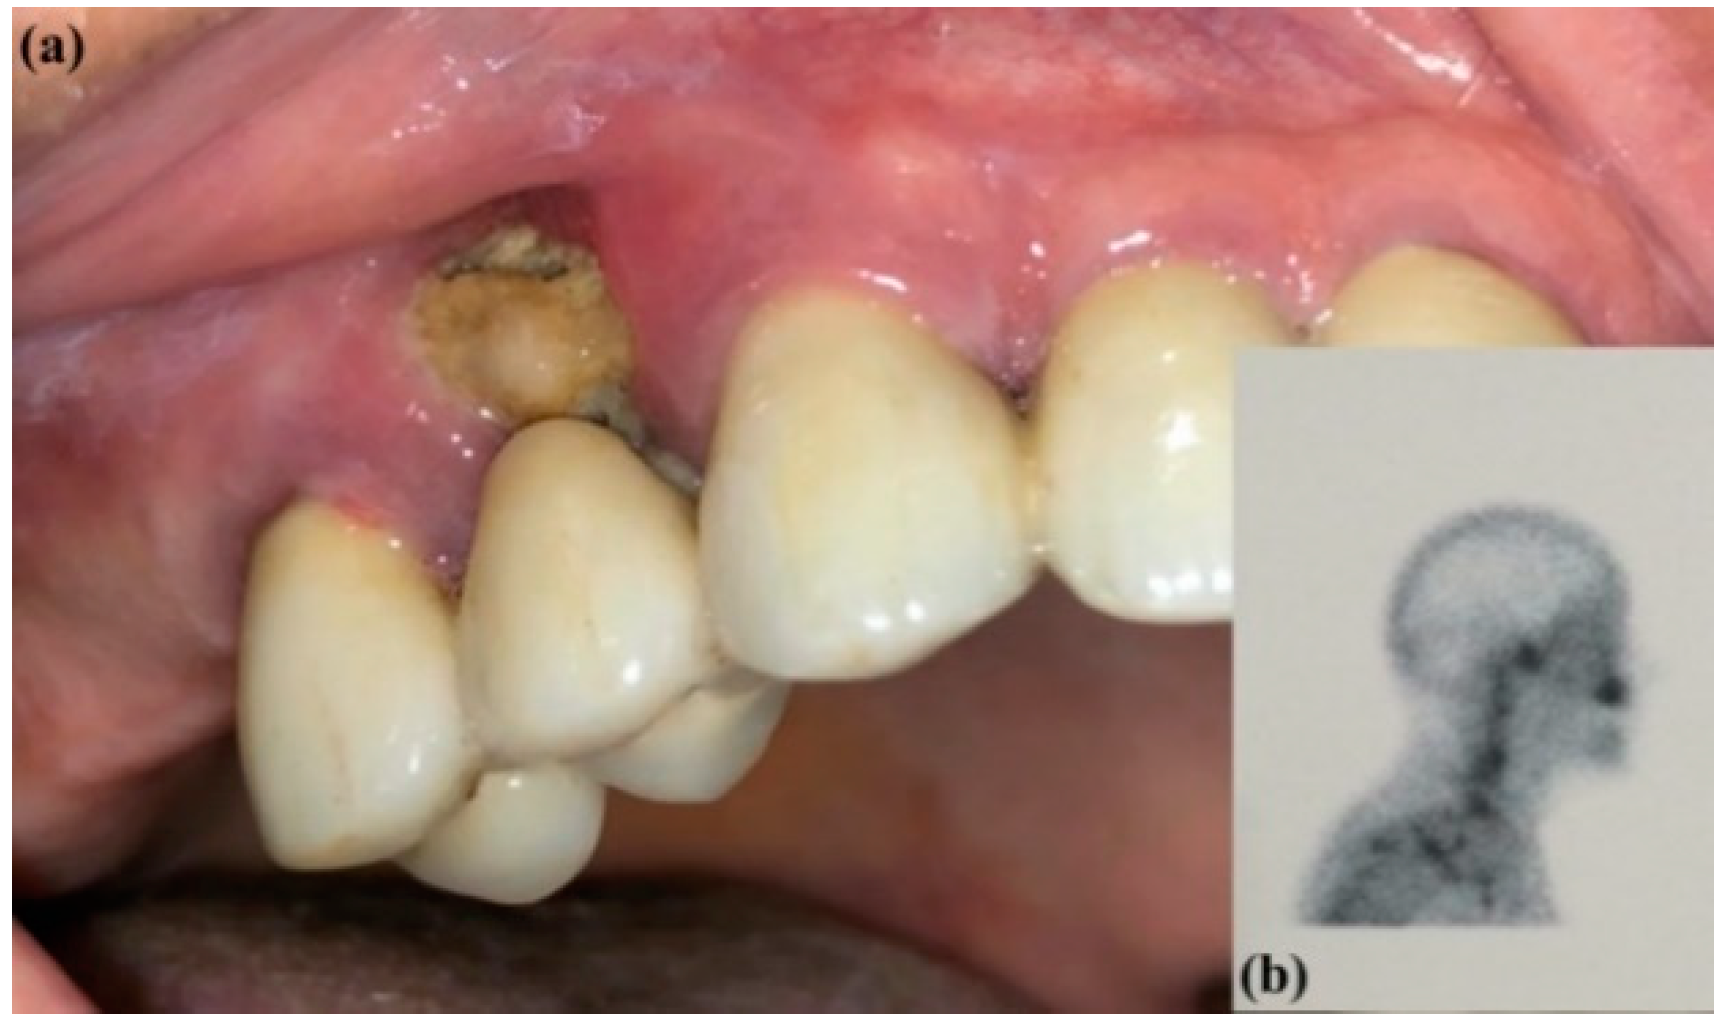

From www.mdpi.com

Dentistry Journal Free FullText Imaging in Patients with Bone Marrow In Jaw This is a rare condition associated with dental extractions and bone therapies often used in cancer treatments, and occurs when jaw bones become uncovered by the gums and lose adequate blood flow. Knowledge of changes in the jaw bone marrow and each tissue’s growth rate is essential. It is also necessary to know when the tooth germ begins to calcify. Bone Marrow In Jaw.

JCM Free FullText Management of MedicationRelated Osteonecrosis Bone Marrow In Jaw This is a rare condition associated with dental extractions and bone therapies often used in cancer treatments, and occurs when jaw bones become uncovered by the gums and lose adequate blood flow. In turn, the radiologic analysis of these lesions requires a systematic approach and a broad consideration of clinical and imaging characteristics to enable reliable radiologic diagnosis. Knowledge of. Bone Marrow In Jaw.